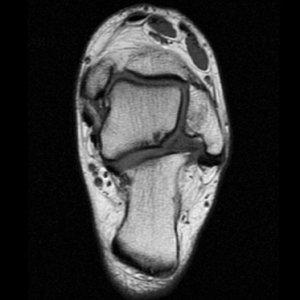

Axial PD fat suppressed FSE

Axial PD fat suppression evaluates the tendons and ligaments of the ankle particularly after acute/subacute injuries. It also is sensitive to talar dome osteochondral defects. Alternatively, a T2 sequence can be used to eliminate magic angle artifact that may occur as the tendons travel around the malleolar turns.